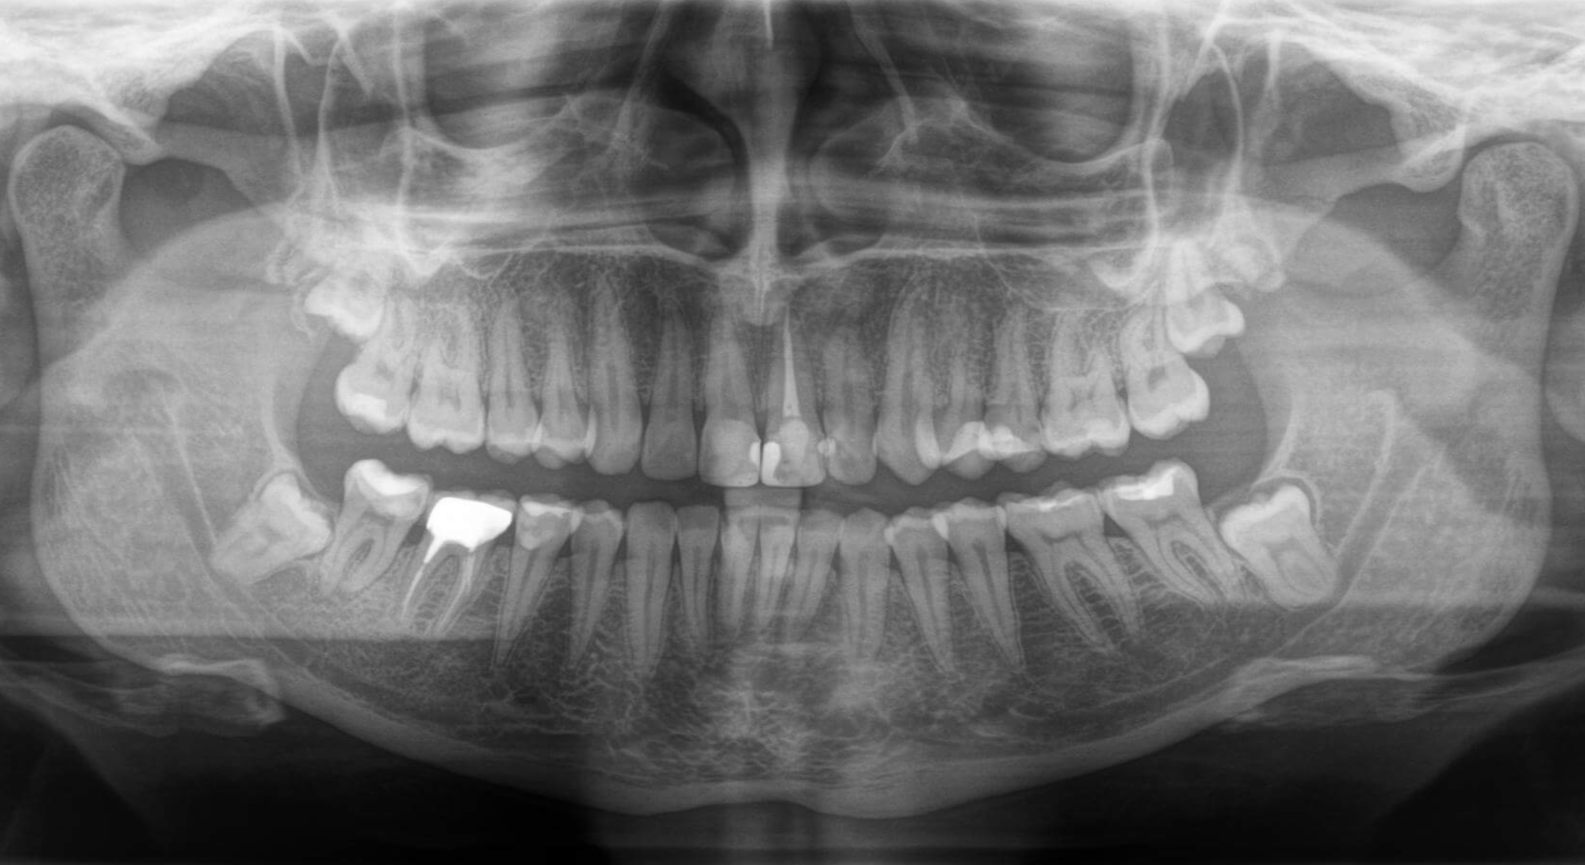

Рентген-діагностика

Дозволяє визначити рівень кістки, виявити можливі причини виникнення пародонтиту і відстежити динаміку лікування